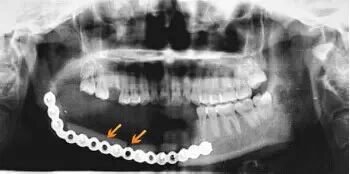

手术切除右侧下颌骨,游离腓骨皮瓣 + 重建钛板重建术后缺损。